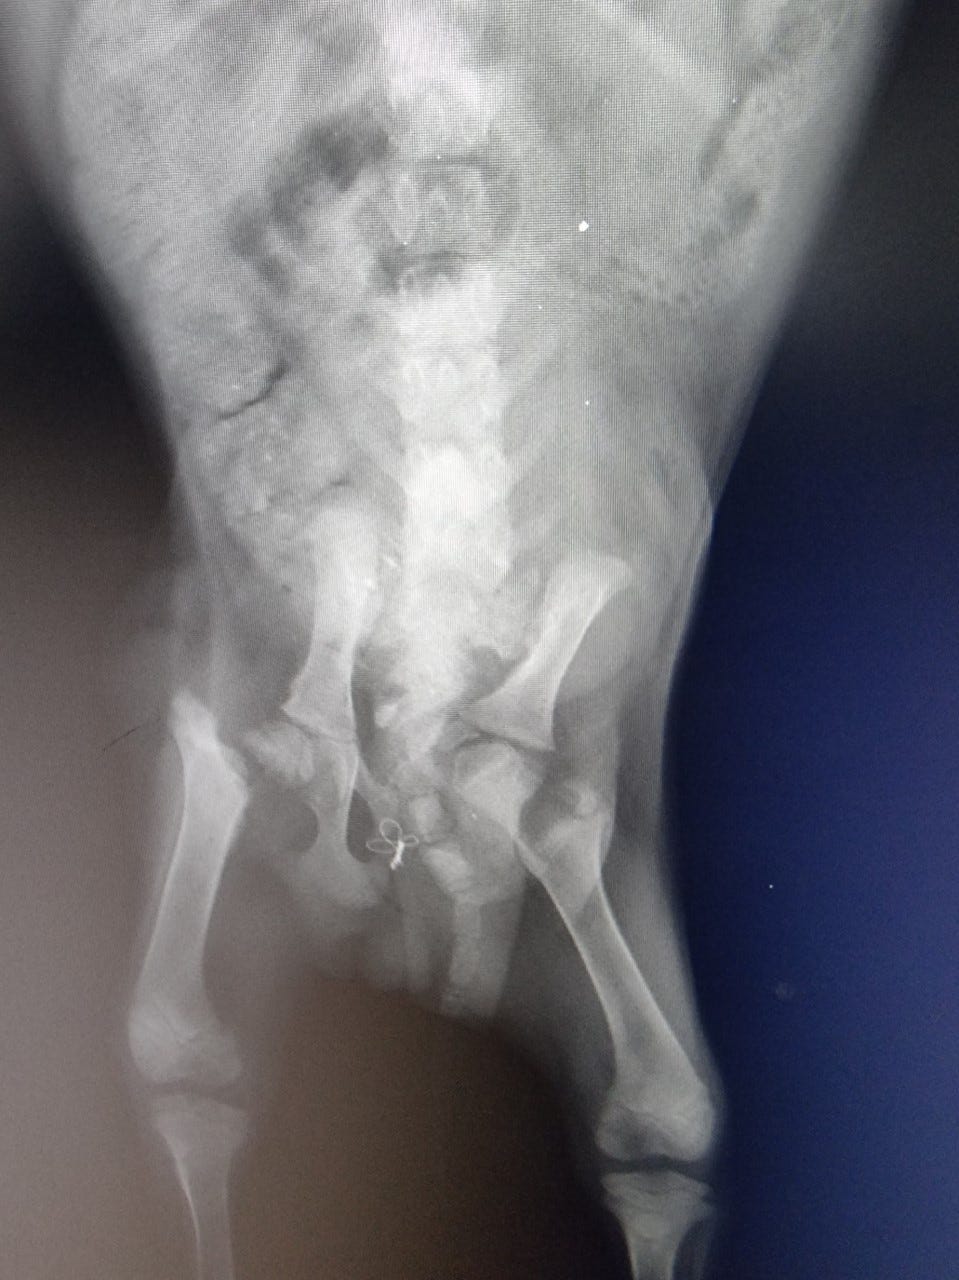

Billy’s original surgery was botched.

He had fragments of bone left in his body & his femur was blocking his bowel. This was an emergency situation as Billy could bot go to the toilet properly. If he had not come under our care he would have died.

Billy needed two further surgeries to correct the damage that the first surgery had inflicted on Billy.